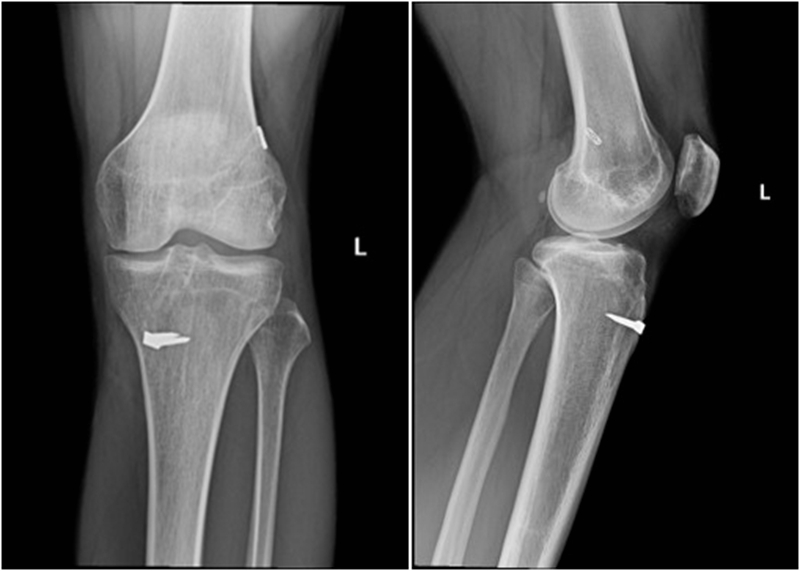

典型病例,张X,男,18岁,因扭伤致左膝关节疼痛伴活动受限1月余入院。

诊断:1.左膝前交叉韧带损伤;2.左膝外侧半月板损伤合并囊肿。

手术方案:左膝关节镜下清理、滑膜切除、外侧半月板部分切除成形、前交叉韧带重建术。

术前X线

术后X线